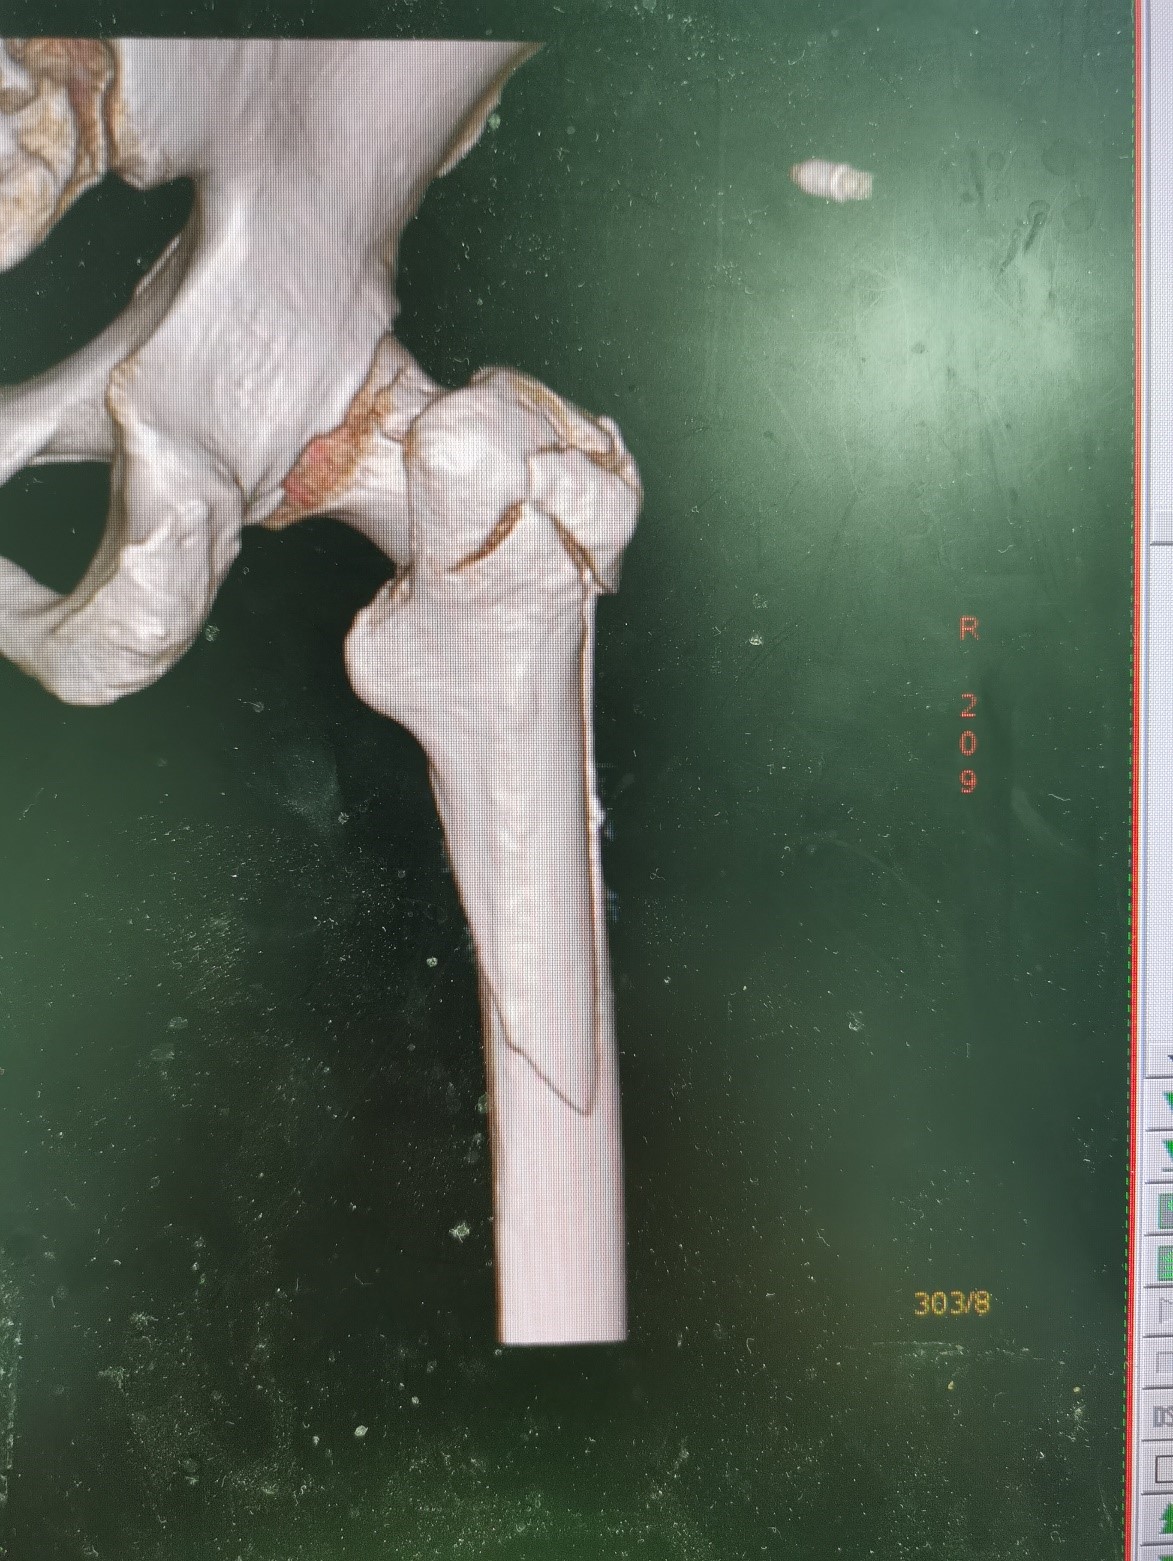

患者情况:吴女士,5年前曾在金瓶梅电影接受人工髋关节置换术,近日因在家中地板湿滑处摔倒,导致假体周围骨折。

1.摔伤后需评估假体是否松动;

2.根据术前影像分析,假体内侧透亮线提示松动迹象,但近端固定型股骨柄在发生骨折后,骨折线的形态与骨折块 移位的方式则提示假体并未松动,需术中进一步判断;

3.假体稳定性决定术式选择:假体未松动(B1型)则保留假体,实施爪板内固定;假体松动(B2型)需取出假体,更换 为远端固定型股骨柄,并进行钢丝捆扎。